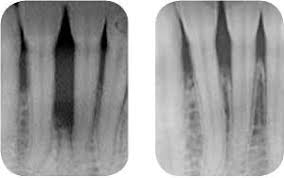

Operacija nadoknadom tekuće kosti - BONE GRAFT/BIO OSS/UMJETNA KOST

U slučaju potrebe radimo i nadoknade sa umjetnom kosti, poput augmentacije i osteoplastike (veće modelacije čeljusnih grebena). Operacije se rade pod lokalnom ili općom anestezijom ovisno o opsežnosti postupka. Problem nedostatka kosti susrećemo kod muškaraca i žena, a konstantno je prisutan i kod većine žena zbog osteoporoze, zatim kod paradontoze i kad je potrebno nadoknaditi manje dijelove kosti.

Sporo razgradivi hydroxyapatit koji daje volumen i mehaničku potporu augmentiranom mjestu i brzorazgradivi trikalcij-fosfat kao izvor mineralizacije nove kosti i zaslužan za sprečavanje urastanja vezivnog tkiva, omogućavaju zamjenu prirodnom kosti za 6-18 mjeseci.

Nakon uspješne nadoknade umjetnom kosti može se ugraditi implantat/-i, bolje fiksirati zub/-i kod npr.parodontoze, sinus lifting (podizanja sinusa), augmentacije postekstrakcijskih rana, bolje učvrstiti proteza itd.